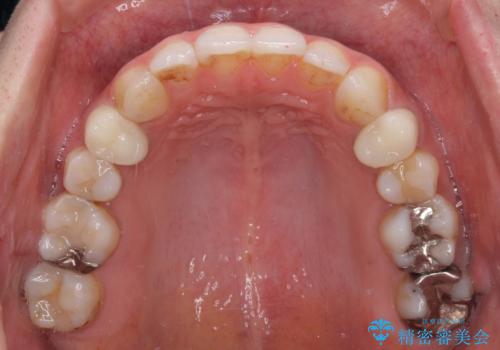

総合歯科治療 矯正治療と失活歯のセラミック補綴治療

- 失活により変色した歯と不揃いな口元を気にして来院された患者様です。

口元をインビザラインにより歯列を整え、その後に失活している奥歯をオールセラミッククラウンにて補綴治療することとしました。

長時間のマウスピース装着と、患者様自身でのゴムかけに協力いただき、自然な口元に仕上げることができました。

気になっていた変色した歯もオールセラミッククラウンで本物の歯のようになり、患者様には大変満足していただきました。